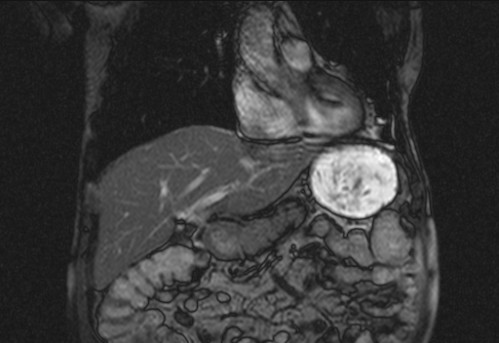

Auffälliges Abdomen bei der Vorsorgeuntersuchung einer älteren Dame

ICD: C64